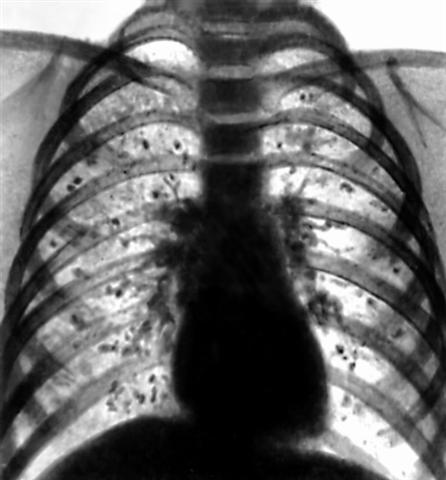

Рис. 1. Множественные кальцификаты в легких у больного хронической формой гистоплазмоэа.